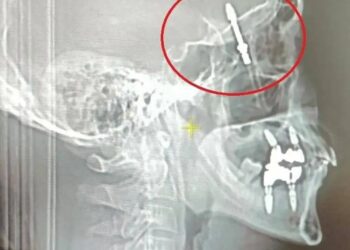

Түркияда тиш доктур имплантты бейтаптын мээсине чейин бурап салган

40 жаштагы Рамазан Йылмаз тиши ооруп менчик клиникага кайрылган. Тиш доктур бейтапты 24 жылдык тажрыйбасы бар адис экенине ишендирген. Дарыгер оорулуу тишти жулуп алып, имплант орнотууну сунуштаган.  Бейтап макул болгон ...